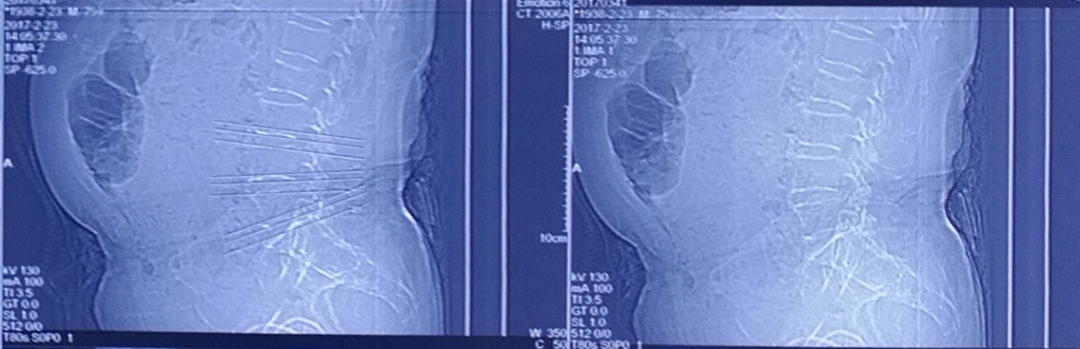

术前CT

术后CT

•      术后3月CT